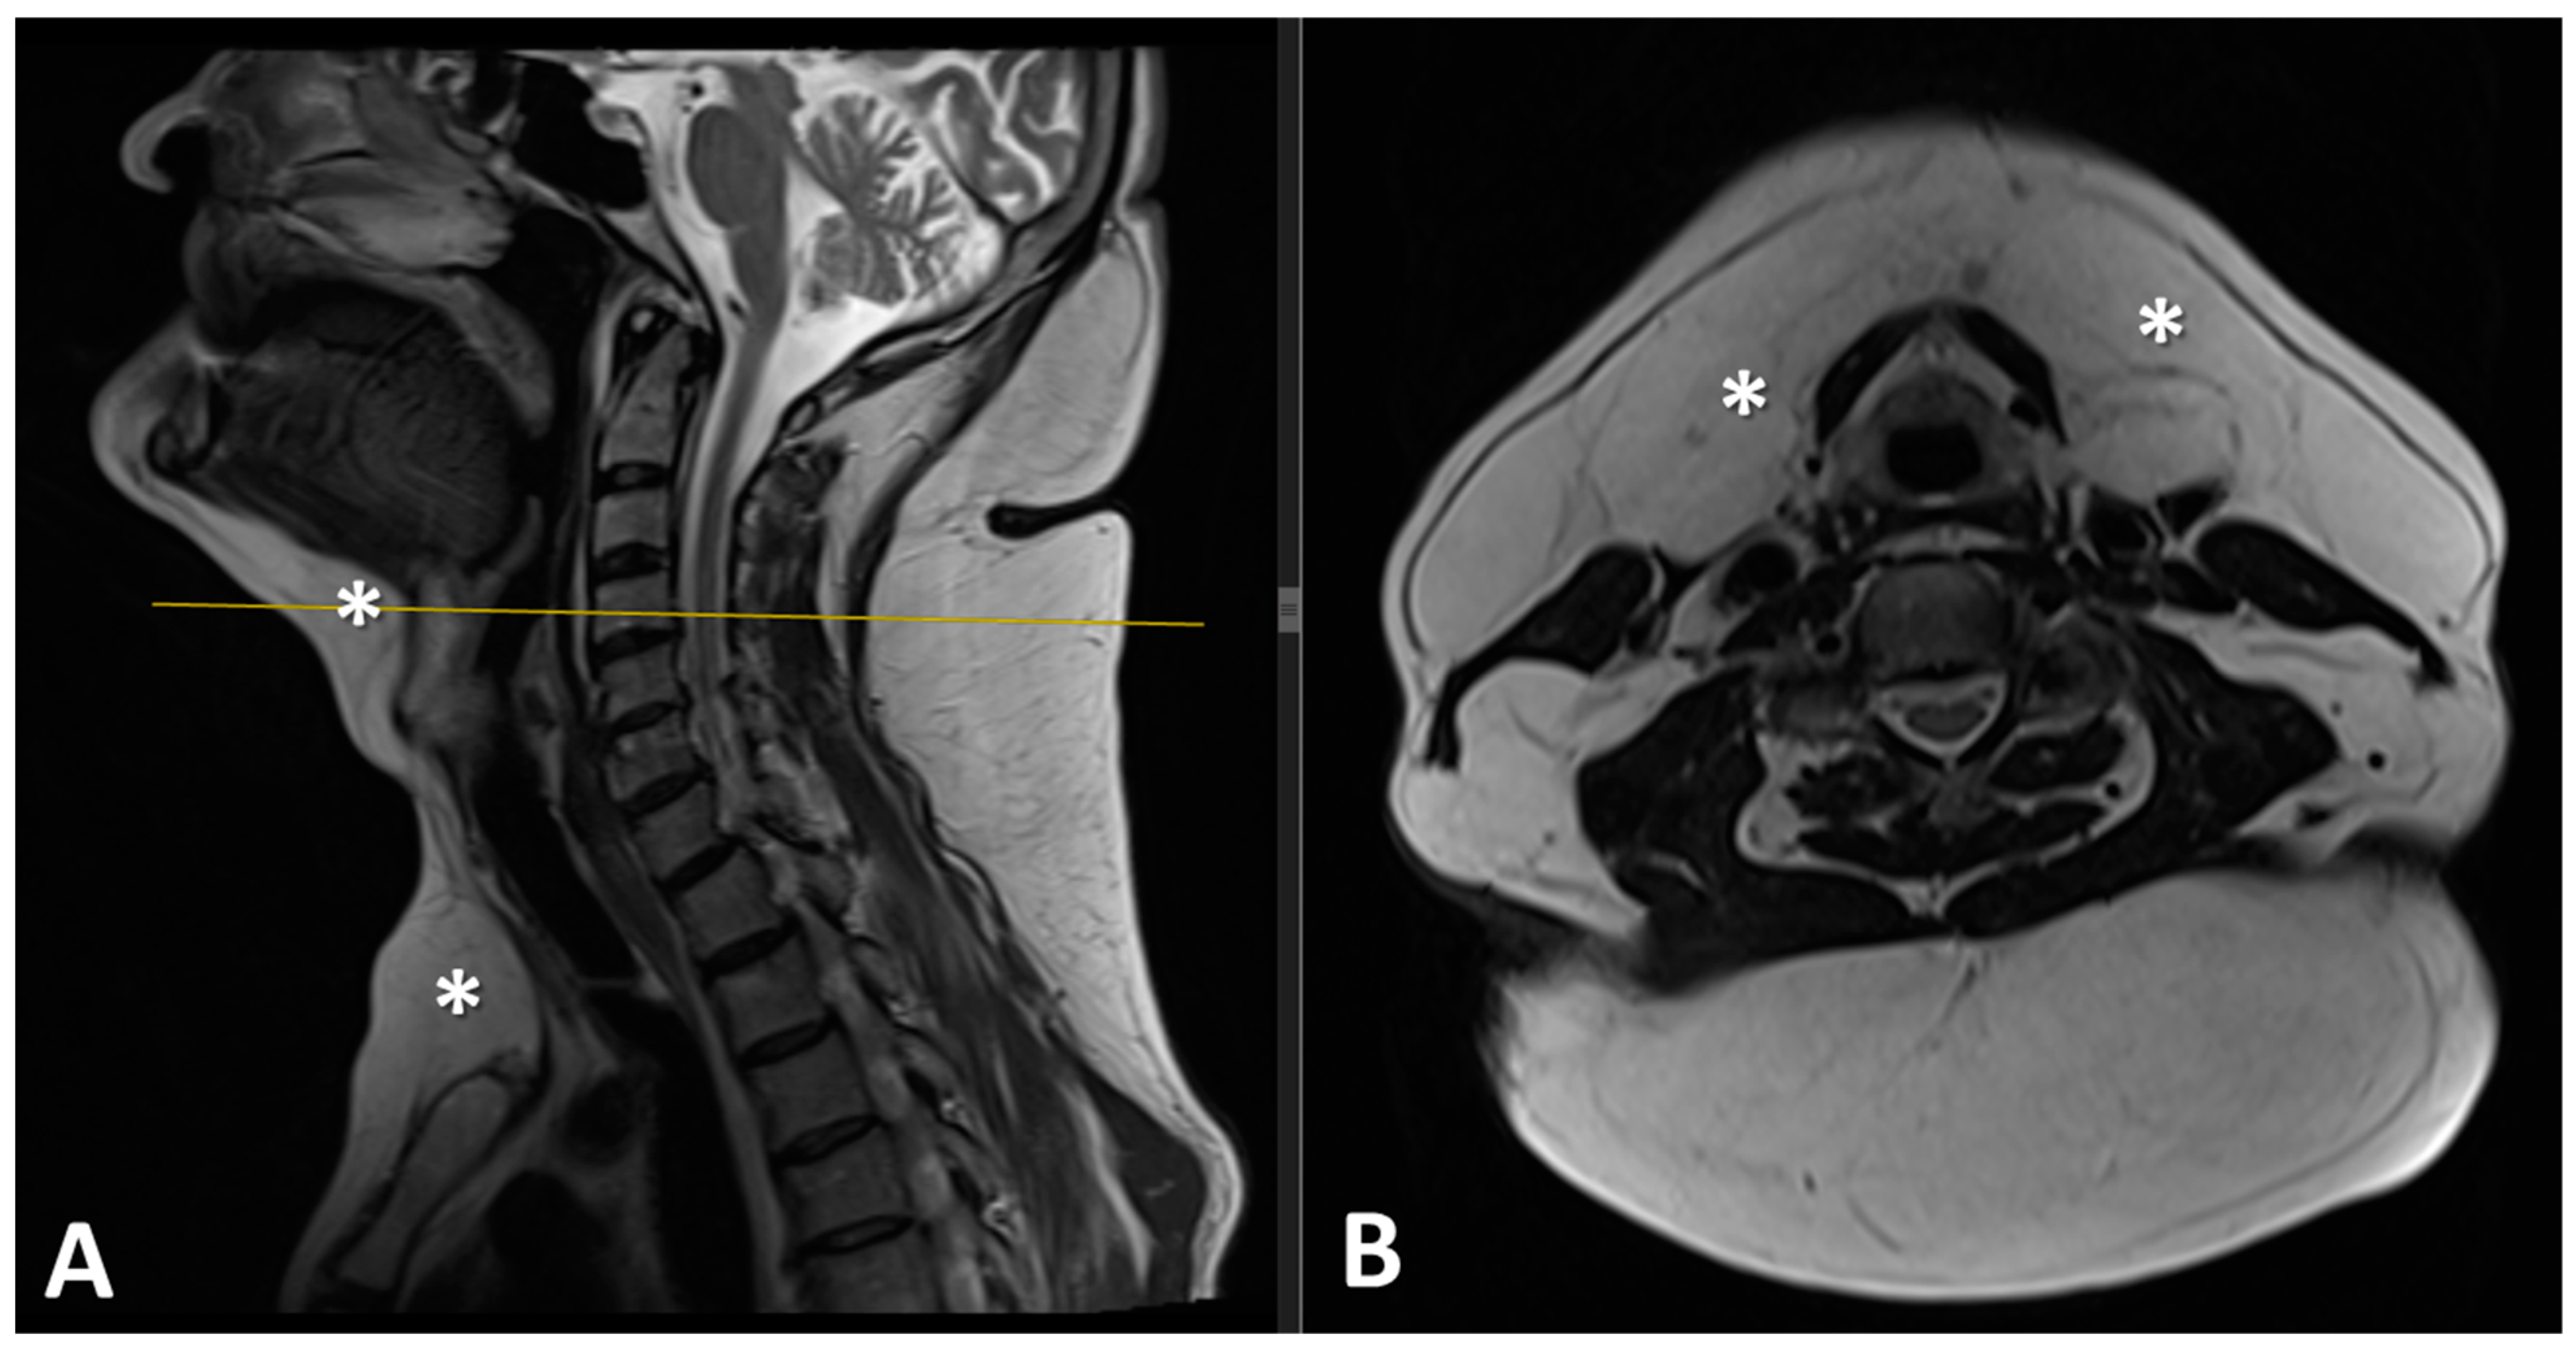

2.2. Imaging Studies

3.4. Diagnosis